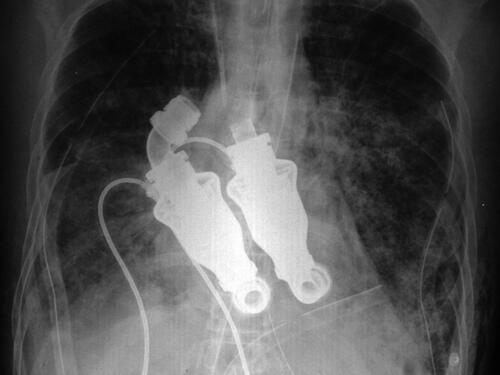

Craig Lewis menjadi manusia pertama di dunia yang bisa tetap hidup meskipun tanpa jantung di dadanya. Semua ini berkat pengobatan spektakuler yang dilakukan oleh dua dokter dari Texas.

Dokter Billy Cohn dan Bud Frazier dari Texas Heart Institute berhasil mengganti jantung milik Craig Lewis dengan sebuah alat pompa yang berfungsi layaknya jantung manusia.

Jantung buatan ini telah menyelamatkan nyawa bapak berusia 55 tahun itu dari penyakit amyloidosis, sebuah penyakit yang menyebabkan tubuhnya memproduksi protein abnormal. Protein-protein inid apat memenuhi organ tubuh hingga organ tersebut berhenti bekerja.

Kini, Lewis bisa dibilang sebagai manusia tanpa jantung pertama yang berjalan di muka bumi. Tak hanya itu, jantung buatan tersebut membuat bapak ini tak memiliki denyut nadi. Hal ini dikarenakan cara kerja jantung buatannya yang tak berdetak seperti jantung asli, melainkan hanya memompa darah terus menerus tanpa henti. Tapi bagaimanapun hasilnya, selama alat ini berfungsi, Lewis akan tetap hidup meskipun tanpa detak jantung dan denyut nadi.